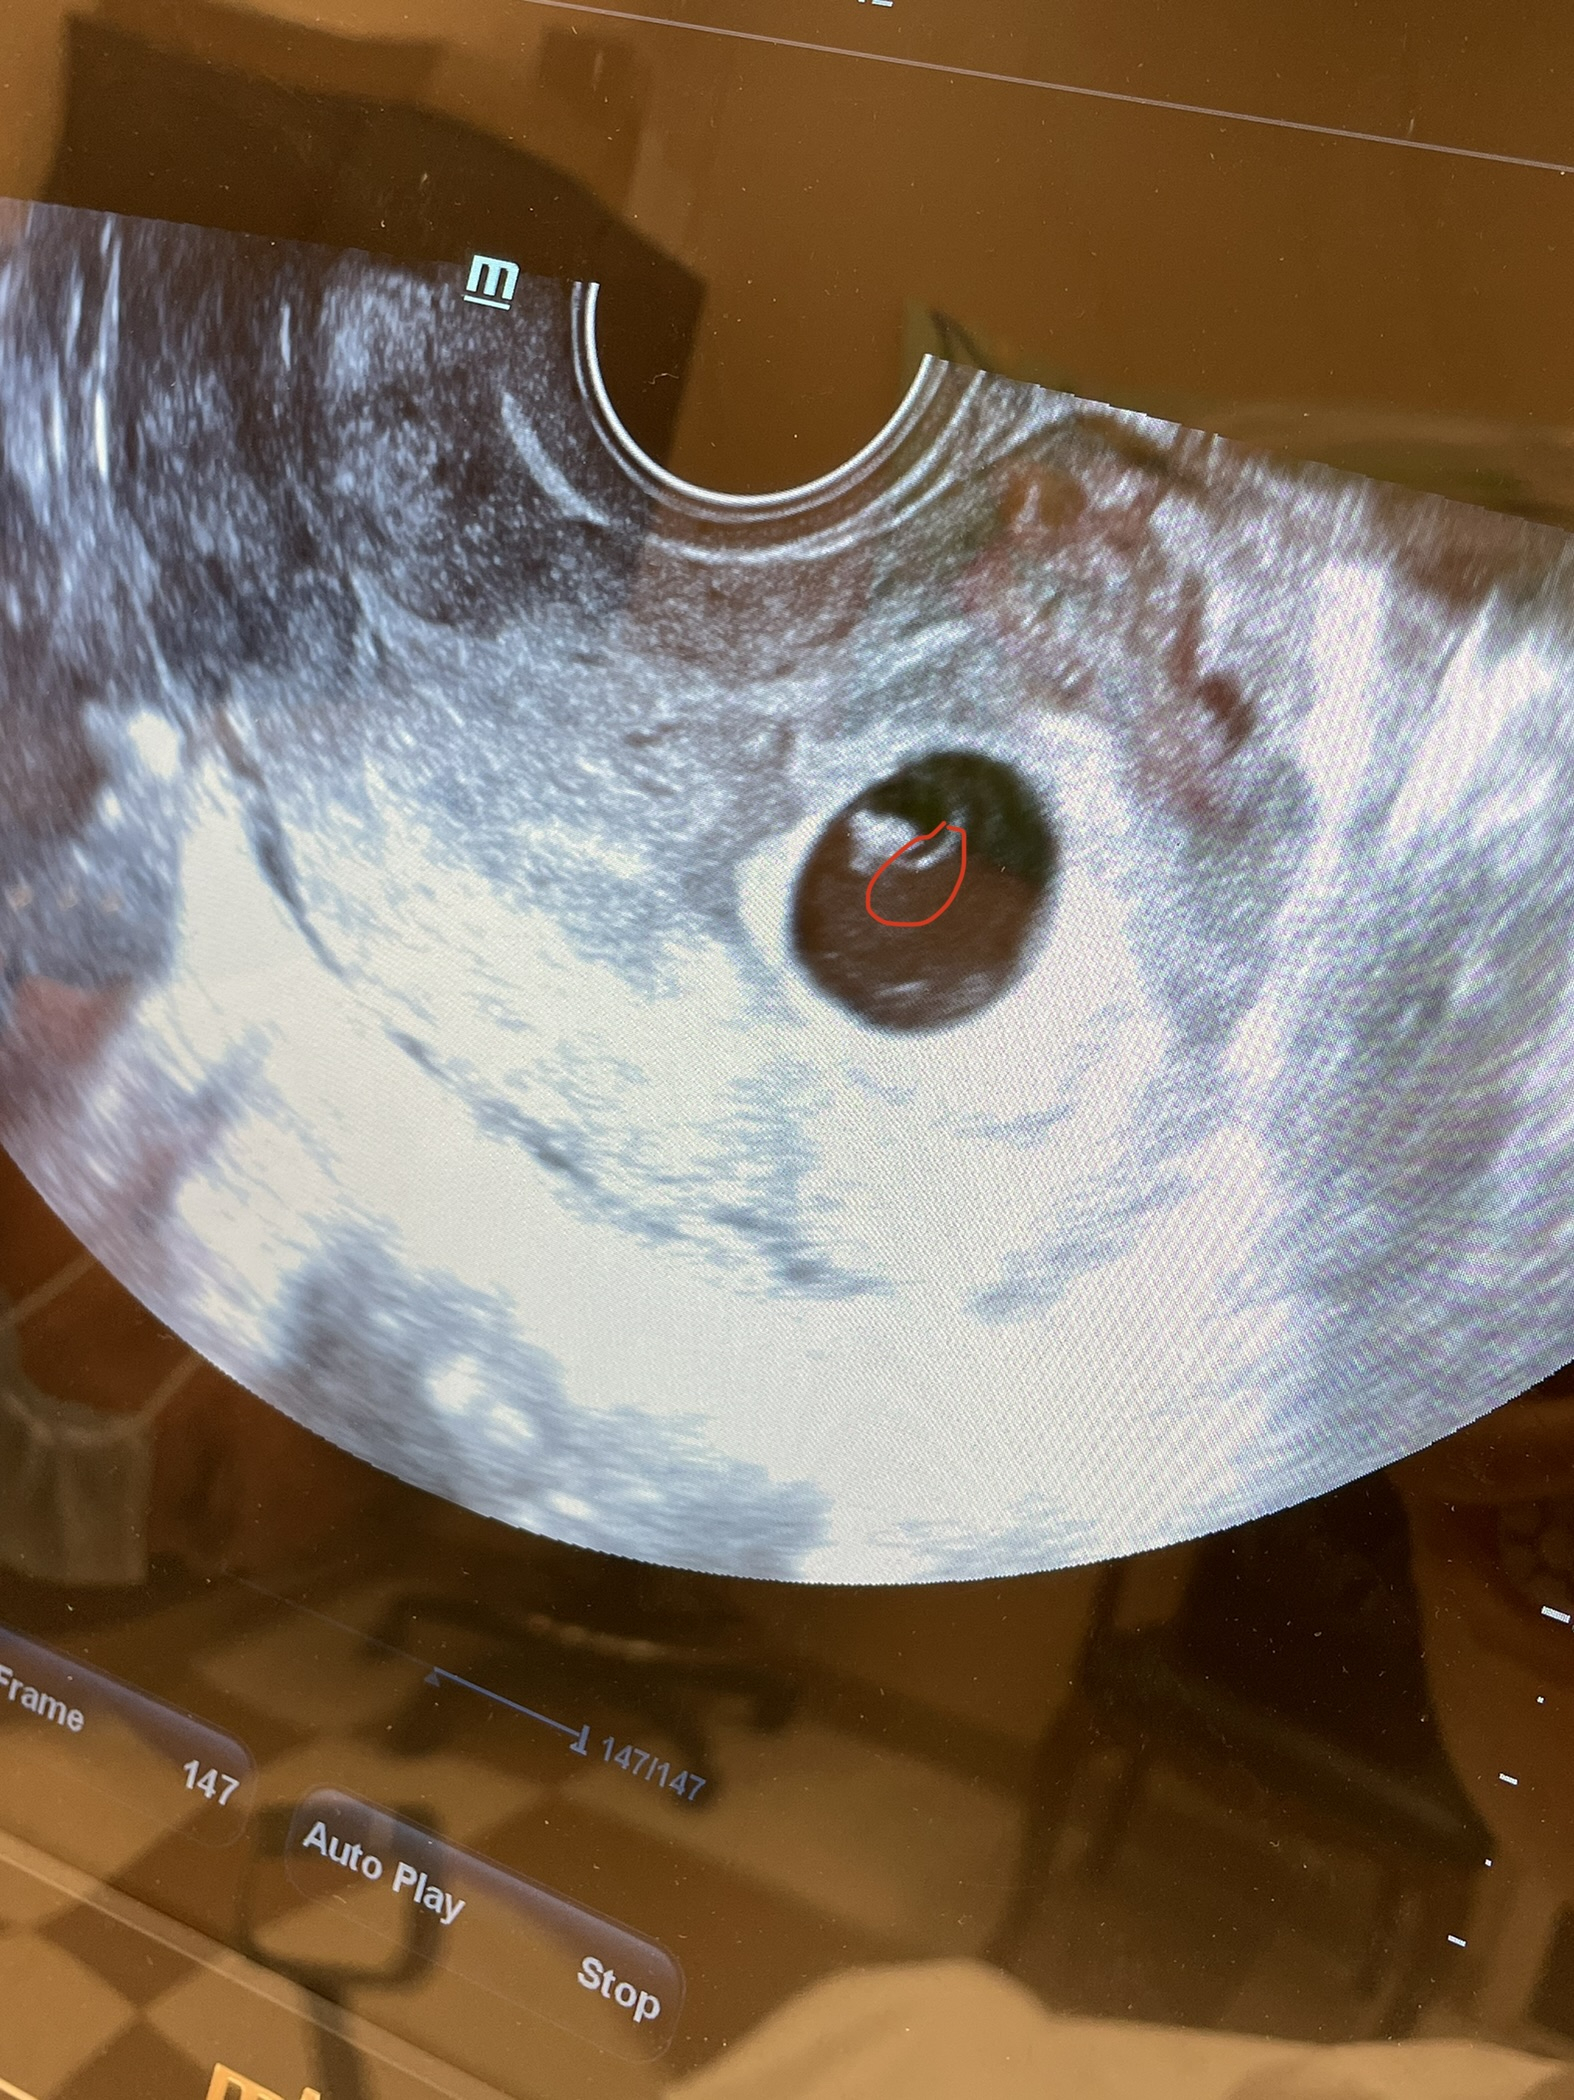

this was my ultrasound on 4/6/21. i measured at 6wks. he said that that was the baby i circled connected to the yolk sac growing. i have had one healthy pregnancy and birth in 2019, and two miscarriages afterwards recently this year and last. I’m nervous and unsure if that is really a baby forming or something in the sac because it doesn’t look much like my daughters ultrasound at 6wks 3+4 days. and we were able to hear a heartbeat with her. but not this time. i go in tomorrow but i don’t want to be too excited if there will yet again be nothing there. Sorry i know im not asking for professional help, just other experiences. i’m thinking way too much about it today since i go in tomorrow morning. also taking progesterone, so hoping its not just masking miscarriage symptoms.